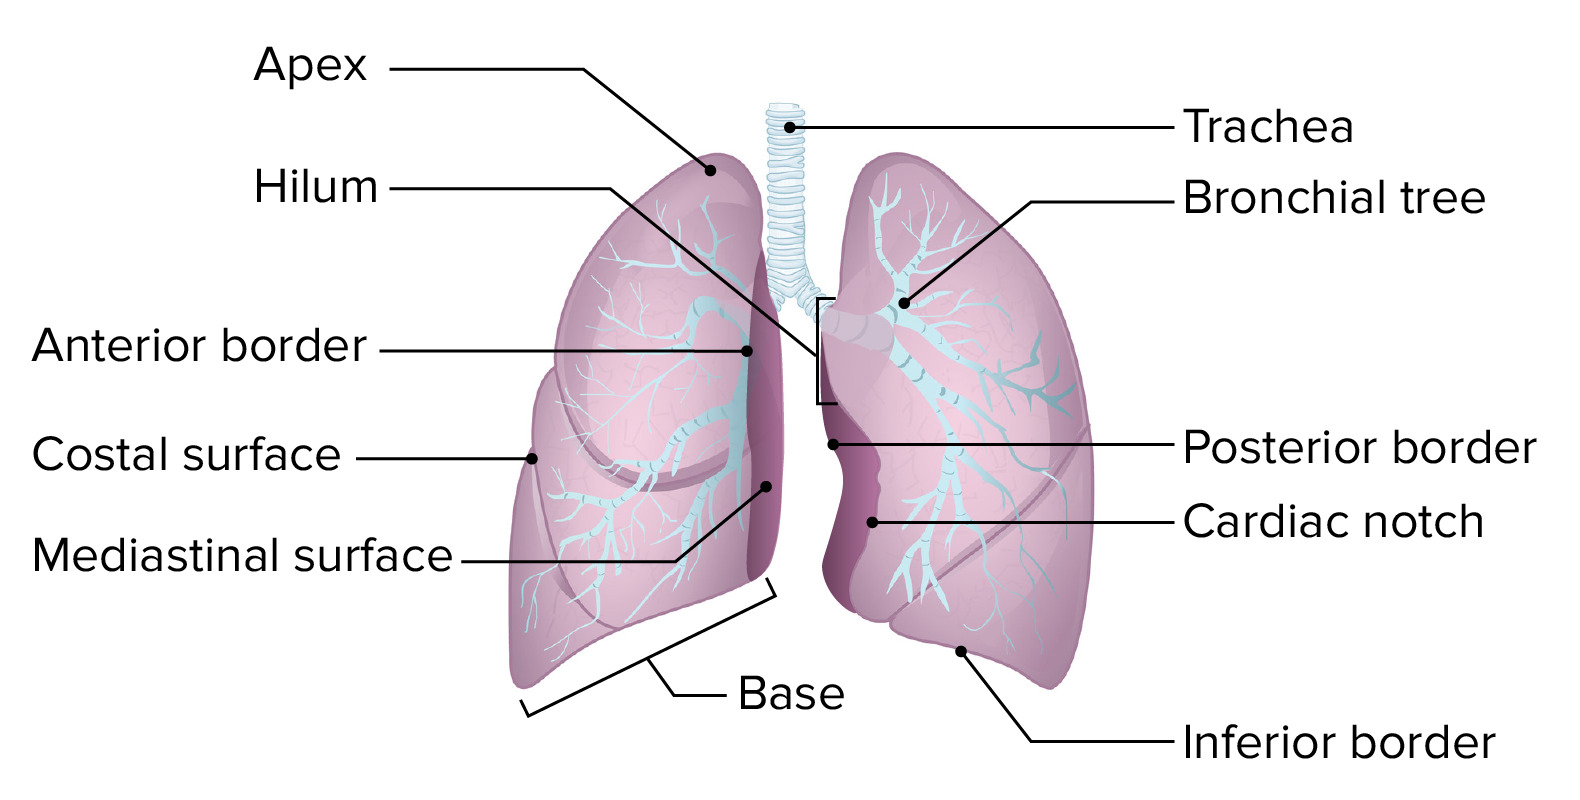

The Lungs - Position - Structure - TeachMeAnatomy

teachmeanatomy.info

teachmeanatomy.info

lungs lobes fissures right left oblique both teachmeanatomy lung structure thorax fig similar position info